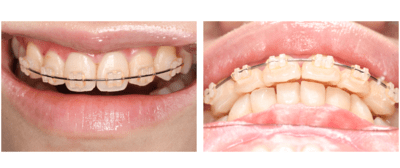

ブラケット・ワイヤー装着

まずはブラケットを装着。審美的になるべく阻害がないように、透明なブラケットを使用した。

2週間後

ワイヤーはまだたわみがあるが正中はやや閉鎖してきた。

更に2週間後

正中はほぼ閉じた。ワイヤーのたわみも無くなってきた。

もうすこし左上2が頬側に出てほしい。

完成。

保定もかねてワイヤー(1622SS)変更。

1ヶ月後

ブラケット除去。

同時に予定していた保定装置のマウスピース用の印象をおこなった。

正中離開、左上2の位置、被蓋関係、全ての改善をすることができた。しかもたったの2ヶ月!